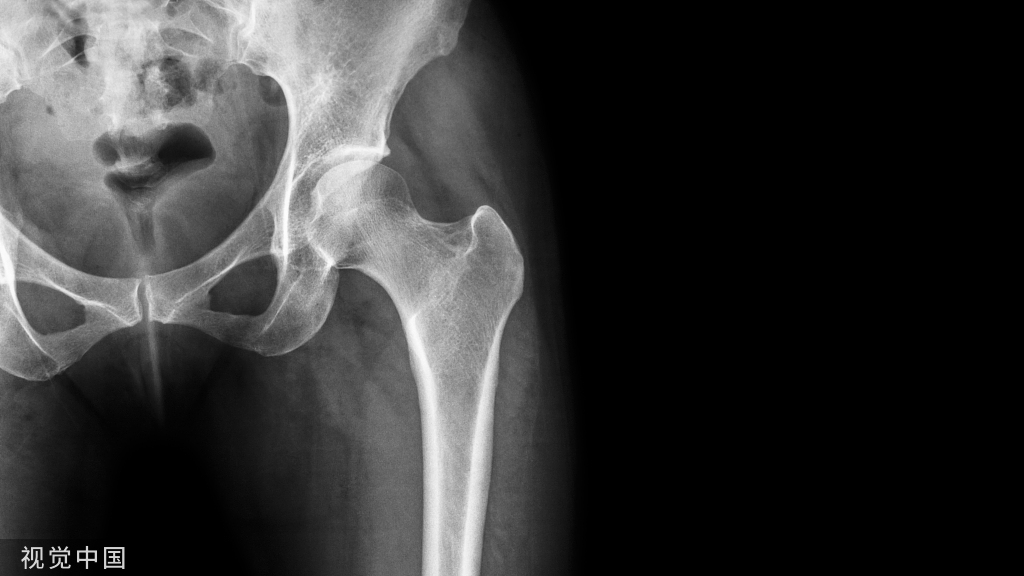

人老了,我们身体各器官系统的功能也会有退化,特别对于绝经以后的女性来说,雌激素分泌减低,间接影响骨骼成骨、破骨作用,使骨生成减少,骨破坏增加。再加上老年人骨质钙磷流失增加,易导致骨质发生脱钙、骨皮质变薄以及骨质疏松等病理变化,直到骨密度及骨强度发生改变,以至于老人在轻微暴力(不慎摔倒)的情况下也会发生骨折,医学上将其称为脆性骨折。常见的脆性骨折发生部位有:尺、桡骨远端骨折、股骨颈骨折、腰椎压缩骨折。

一边屁股着地摔倒,也是一种最常见的危险姿势,这种姿势容易导致髋部骨折,包括股骨颈骨骨折及股骨粗隆间骨折,尤其是中老年人。